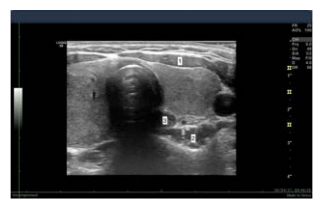

A ultrassonografia cervical, um dos métodos auxiliares mais disponíveis atualmente, não emite radiação ionizante e não tem custos importantes após a aquisição do equipamento. Esse método permite a classificação de diversas patologias e serve como o primeiro método de acesso diagnóstico por meio de punções guiadas e, algumas vezes, intervenções como aspiração, alcoolização ou ablação. Contudo, é um método que requer grande conhecimento anatômico para a correta categorização das estruturas.

Observe a imagem a seguir, na qual se identificam três marcas anatômicas em uma ultrassonografia cervical.

Na imagem acima, os números 1, 2 e 3 correspondem, respectivamente, ao(à):